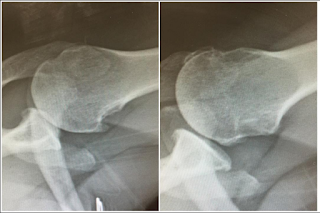

The left is before surgery and the right was taken yesterday. See how there's no space between the bones on the left? That's no good. See how there's space on the right? That's good. Essentially I'm doing fine and only have to go back if something major happens. Even if I dislocate it, I have can't even go to the ER, I have to go immediately to the orthopedist.